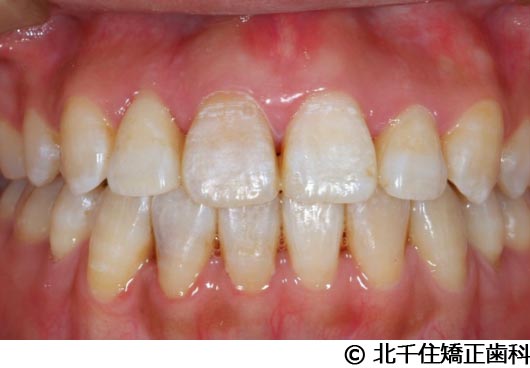

【症例2】上顎前突症

- 治療前

- 治療中

- 治療後

- 治療名

- 上顎前突症

- 費用

- 1,399,000円(税込)

- 期間

- 3年6ヵ月

- 治療回数

- 42回

- 通院頻度

- 1ヵ月ごと

- 年齢・性別

- 19歳10ヵ月・男性(初診時)

治療内容

-

患者様の症状

主訴:出っ歯、口元の突出、横顔をきれいにしたい

治療方法

骨格性の上顎前突、上下顎第一小臼歯4本及び上顎第二大臼歯を抜歯して矯正用アンカースクリューを併用してワイヤー矯正治療(セラミックブラケット)。

治療結果

骨格性上顎前突に対し、抜歯および矯正用アンカースクリューを併用した矯正治療により歯列および咬合関係の調整を行った症例である。治療後は保定装置を使用し、歯列および咬合の安定維持を目的として定期的な経過観察を行っている。

※治療結果は個人差があります。

治療を行う上での注意点(リスク・副作用)

歯磨き不良に伴うカリエスや歯周病、顎関節症、歯根吸収など。